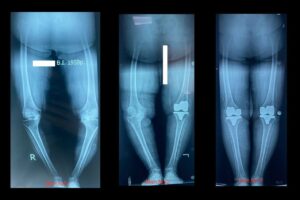

photo_2023-12-13 19.48.45